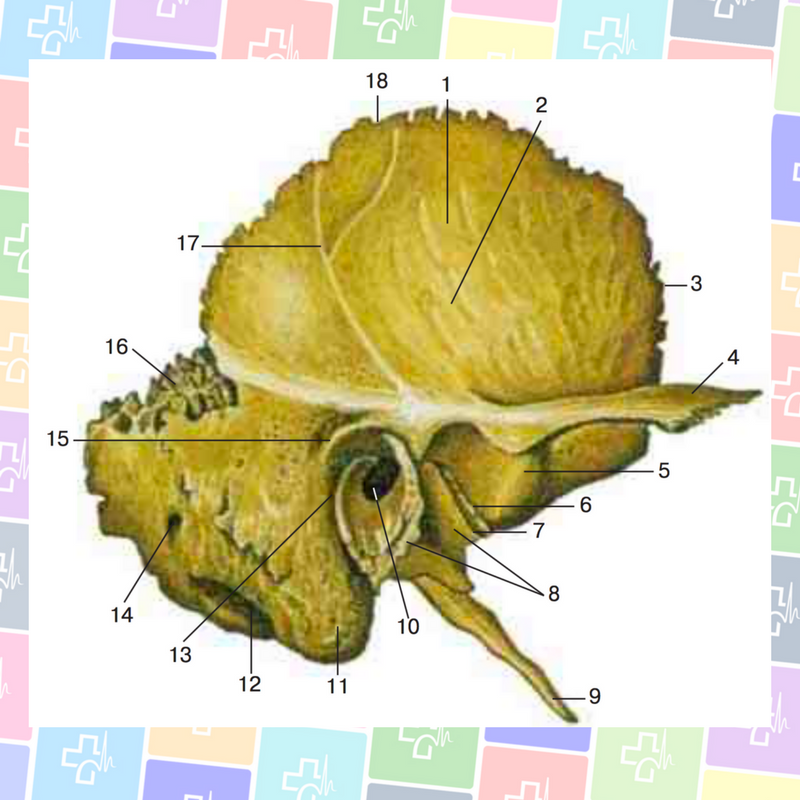

Анатомия и особенности фиссуры петротимпаника